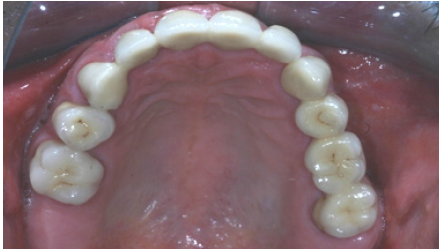

Figure 17: Final restorations occlusal view of the maxilla.

Preparations for veneers, final result

In order to optimize final aesthetics the 5 mandibular anteriors were prepared for all ceramic restorations. Four all ceramic veneers (E-max Ivoclar Co, Liechtenstein) and an all ceramic crown (#42) completed the final restorations. A final occlusal splint was also fabricated chairside (prior to the final cementation of ceramic veneers) for the protection of final restoration and control of TMJ function (Figure 19,20). Minimal occlusal modifications of the splint were necessary after final cementation of mandibular anteriors. The final radiographic examination was kept as a record for future re-examinations (Figure 21). Finally, the patient was enrolled to a 3 months recall program. In each recall and maintenance visit, the periodontal tissues, the abutments and the stomatognathic system were thoroughly examined, preventive regimens were applied and patient compliance was assessed. Two years later, the excellent periodontal condition and performance of the restoration was registrated (Figure 22-24). The patient complied with proper oral hygiene, reduced smoking and adopted a regular use of the occlusal splint. Strict recall and maintenance visits were necessary for long term success of this full mouth rehabilitation. The patient stopped smoking immediately after 6 months and changed nutritional habits in order to eliminate secondary caries.